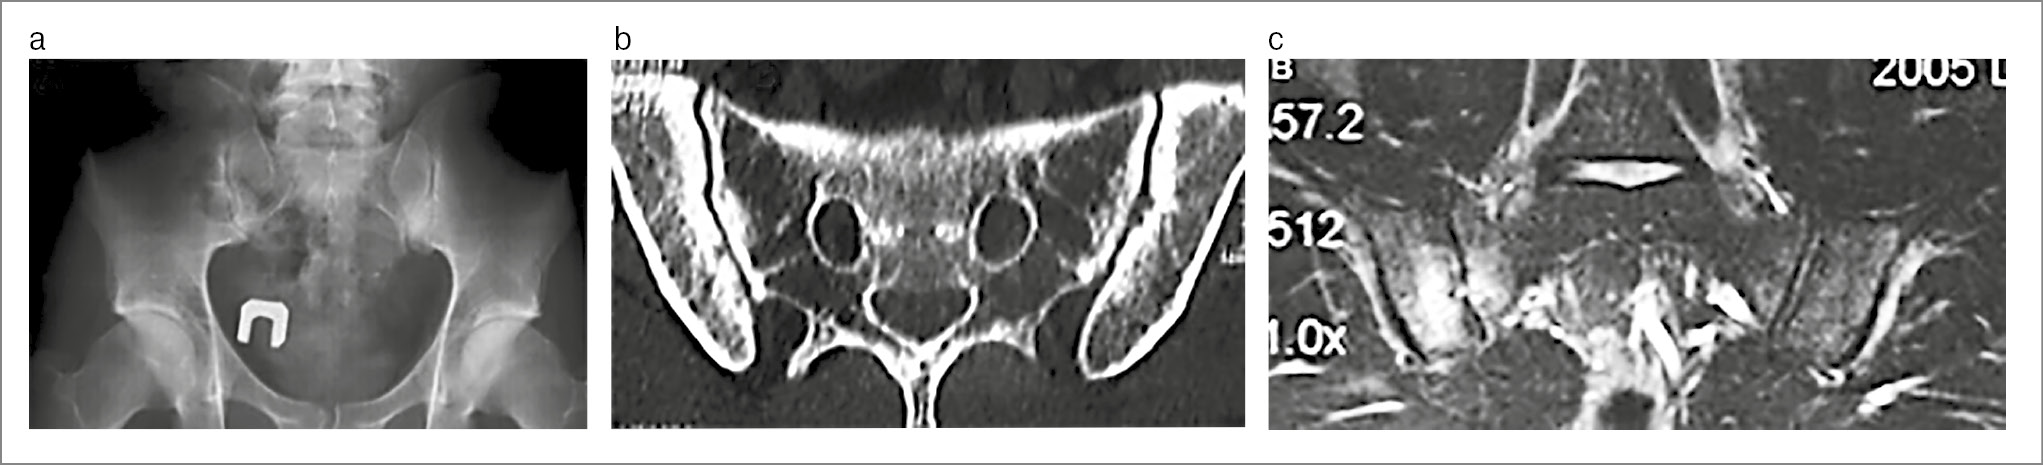

Пациентка В. 29 лет направлена на консультацию в 2023 г. с подозрением на АС. Жалобы на боли в нижней части спины и ягодиц, которые впервые остро возникли на 9-м месяце беременности (за 4 года до настоящей консультации), были стойкими и очень интенсивными. По результатам МРТ (рис. 1) сделано заключение о наличии сакроилиита. После родов боли продолжались, но постепенно стали менее сильными и непостоянными. Скорость оседания эритроцитов и уровень СРБ не повышались. Обнаружен HLA-B27. Установлен диагноз АС. Во время осмотра пациентки осанка существенно не нарушена, движения в позвоночном столбе не ограничены и безболезненны, болезненность при пальпации гребня левой подвздошной кости и в проекции левого КПС. Пересмотр МРТ четырехлетней давности позволил обнаружить стресс-переломы крестца с обеих сторон и массивный отек костного мозга вокруг линий переломов. Повторное МРТ-исследование (2023 г.) показало, что отек костного мозга в крестце отсутствует. На рентгеновском снимке признаков сакроилиита, нарушений целостности крестца не найдено. Рентгеноостеоденситометрия: показатели минеральной костной плотности в поясничном отделе позвоночника и проксимальном отделе бедренной кости в норме. Предположение об АС отвергнуто, установлен диагноз заживших (заживающих?) стресс-переломов крестца.

Рис. 1. Пациентка В. 29 лет. Стресс-переломы крестца, развившиеся на 9-м мес беременности. МРТ (коронарная проекция, режим STIR): в обеих боковых массах крестца отмечаются обширные зоны сигнала повышенной интенсивности (отек костного мозга), на фоне которого прослеживаются линии переломов (указаны стрелками).